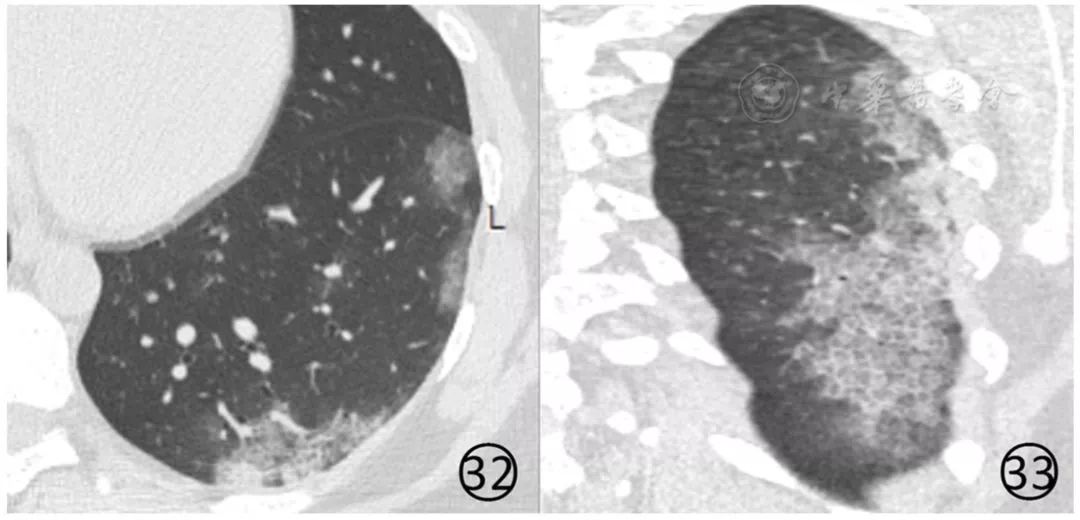

③有流行病学史,肺内有明显的病变,新型冠状病毒核酸检测前几次阴性,最终为新型冠状病毒核酸检测阳性(图32,图33)。

图32,33 女,34岁。患者母亲确诊为新型冠状病毒感染的肺炎。本例新型冠状病毒核酸检测前2次阴性,第3次阳性。CT平扫初次检查,肺窗(图32,33)显示左肺大片状磨玻璃阴影,其内伴有细网状影,呈"铺路石征" ,内可见增粗的血管影